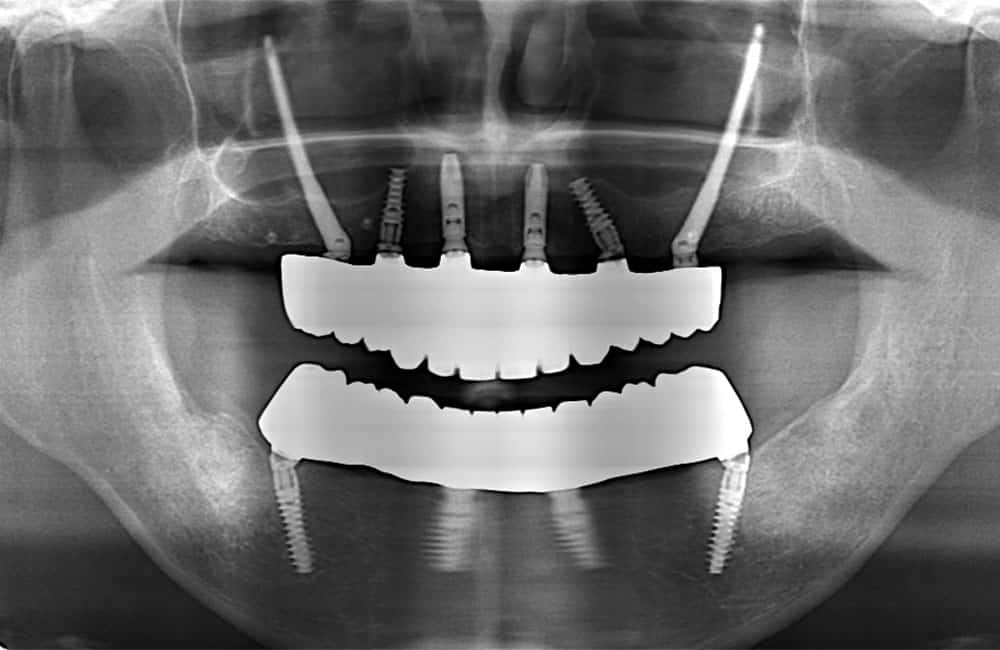

他院でザイゴマインプラント治療を受けた後、仮歯の噛み合わせが悪いため噛みづらく顔貌も変わってしまった。また頬に違和感を感じたため当院を受診。

術前のCT画像

左右のザイゴマインプラントが頬骨から大きく飛び出し頬を触ると違和感がある -

術後のCT画像

前方のインプラントは残し、他院埋入のザイゴマインプラントを除去し、同時に新しいザイゴマインプラントを適切な位置に再埋入を行っております。治療後数年経過しておりますが良好な状態を保っております。